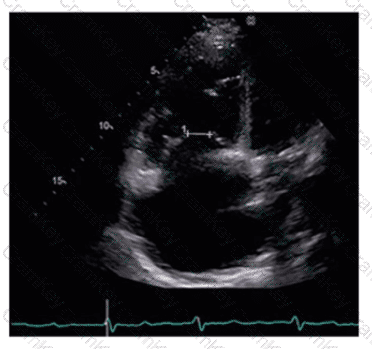

What can be concluded about the tricuspid valve demonstrated in this image?